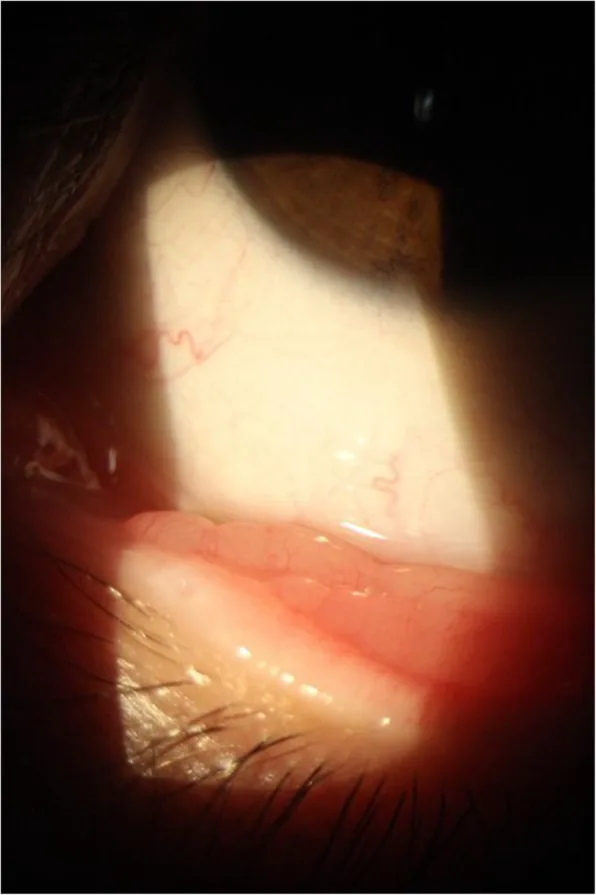

- 結膜病変:顆粒状で肉質、赤色の軟部組織病変である。表面に多数のピン頭大の白〜黄色斑点を認め、これは成熟胞子嚢を反映する。血管に富み脆弱で、接触すると容易に出血する

- 結膜病変の形態:眼瞼結膜では有茎性(pedunculated)、球結膜では眼瞼の圧迫力により扁平・無茎性(sessile)となる